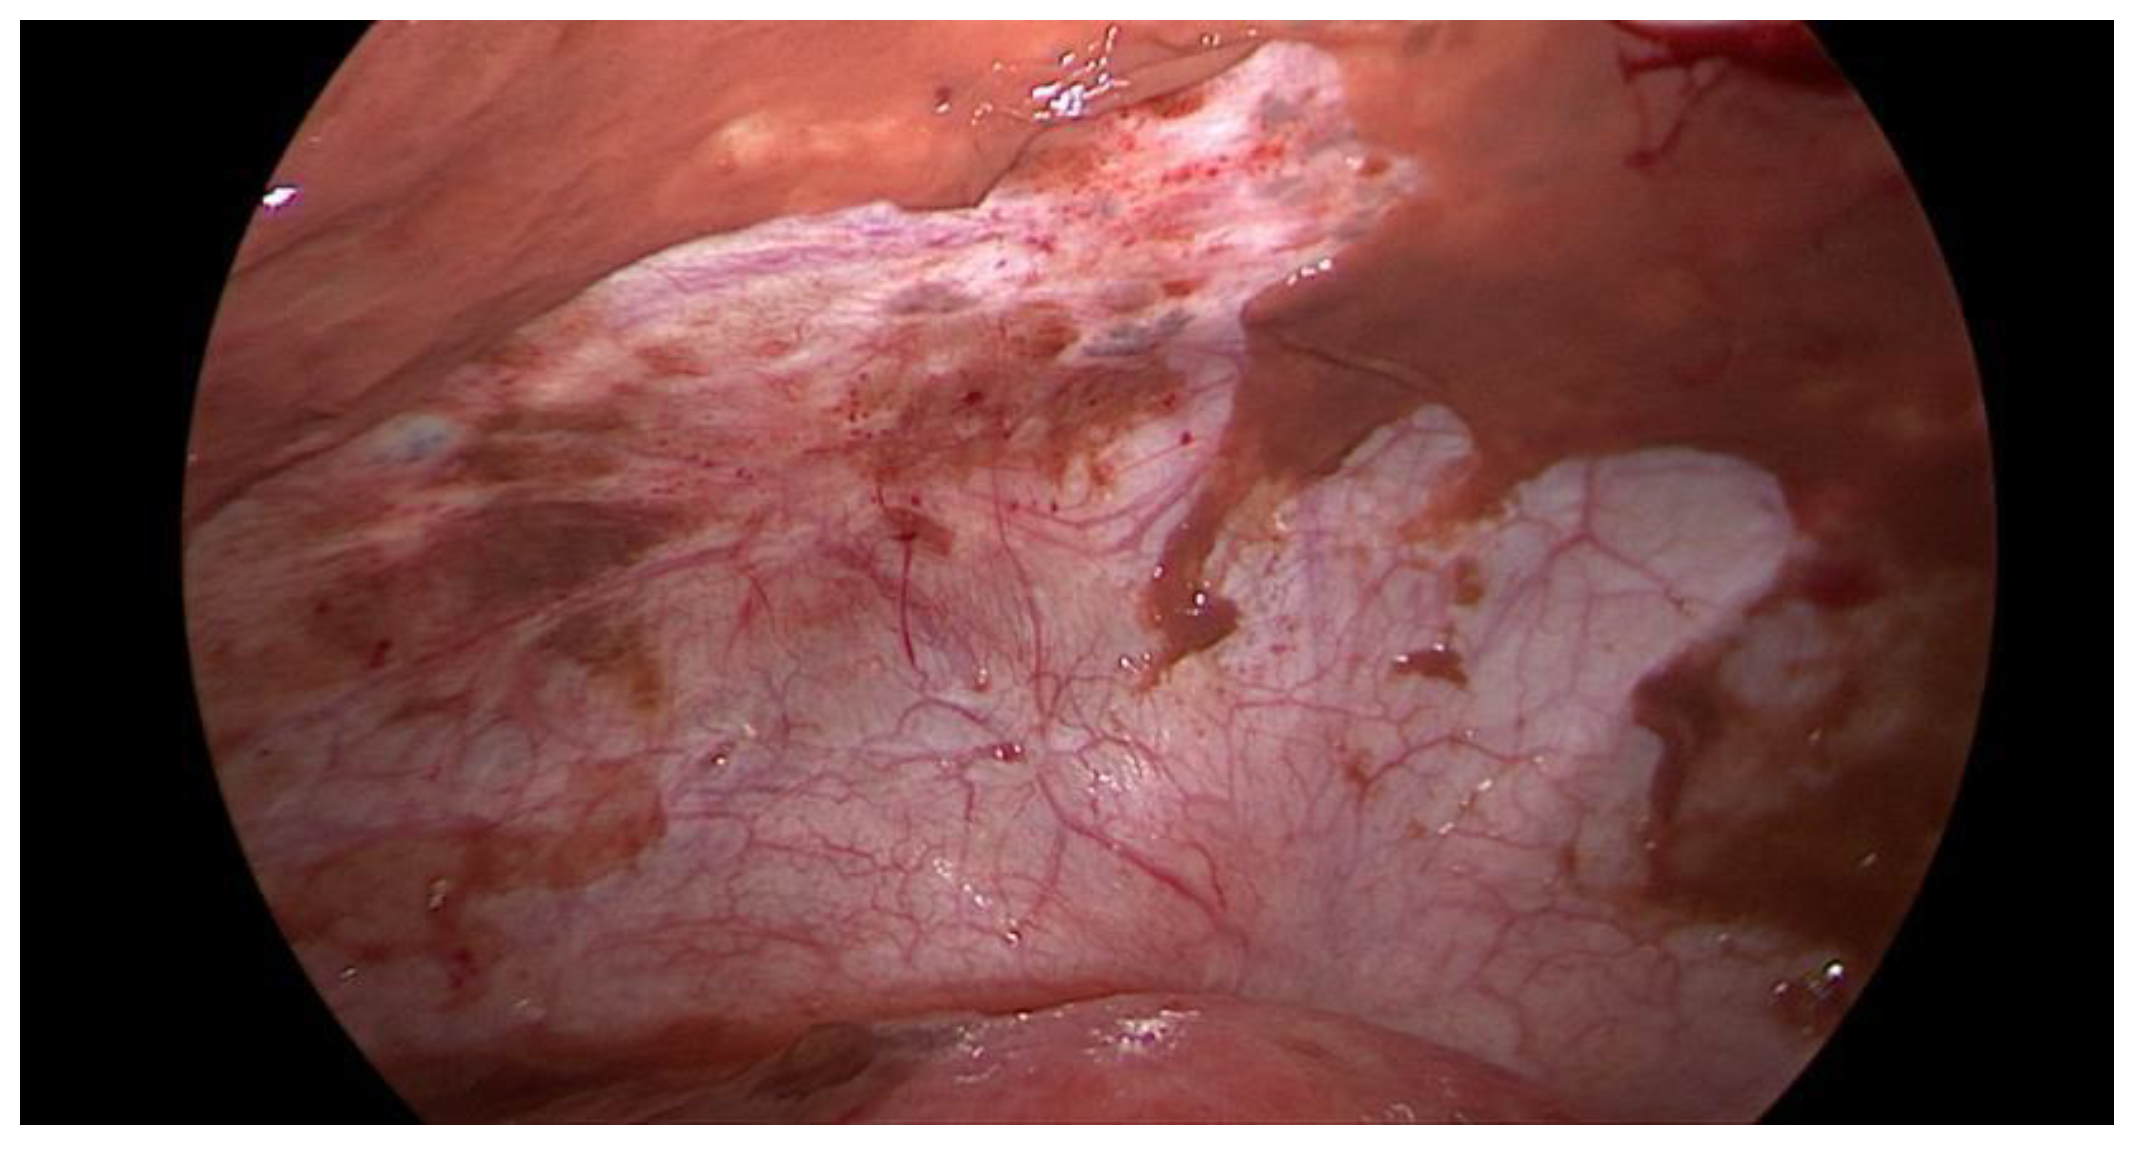

Data collection: The patients’ backgrounds, clinical symptoms at admission, sonographic and laboratory assessment, as well as intraoperative findings were recorded. Patient demographic data included age, menopausal status, presence of dysmenorrhea, history of endometriosis surgery, and use or non-use of hormonal downregulation therapy for endometriosis. Pre-operative laboratory tests included white blood cell (WBC) count, serum C-reactive protein (CRP) level, and serum CA125 level, and all patients underwent transvaginal sonography (Figure 1) on admission as part of the emergency diagnostic assessment. The maximal diameter and the location of the endometriomas were noted. The intraoperative findings included the location of the ruptured endometriomas (Figure 2 and Figure 3), the presence and classification of endometriosis according to the rASRM [16] and #ENZIAN [17] systems, and, lastly, total blood loss.

Figure 1. Sonographic display of a ruptured endometrioma of the right ovary in a 28-year-old woman with sudden onset of abdominal pain.